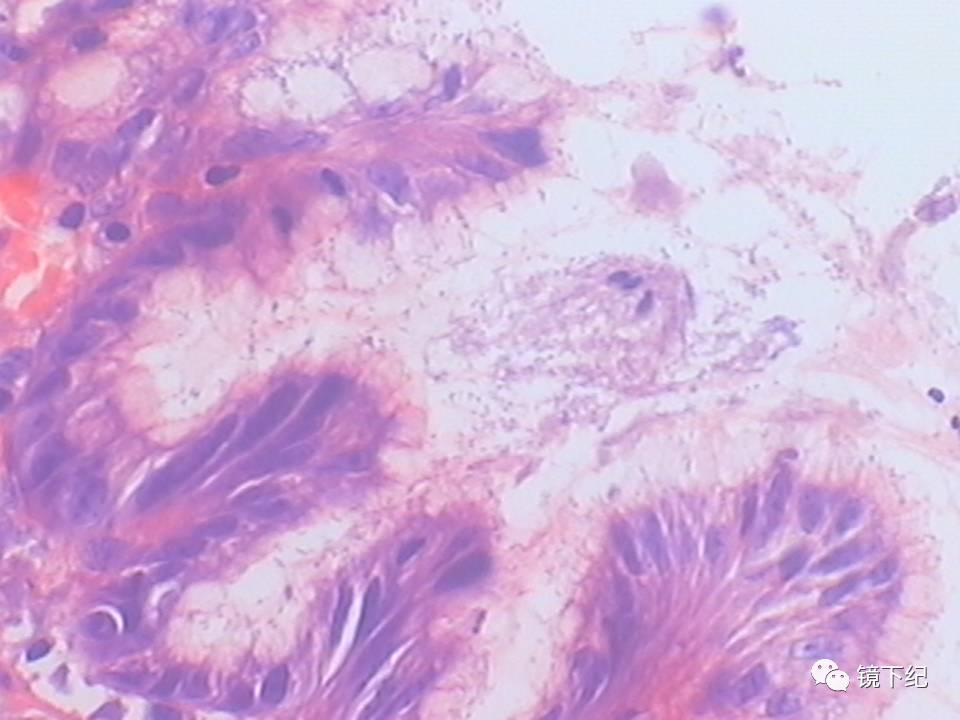

那么如何才是真的胃有毛病需要治疗呢?其实认真的胃镜检查+病理切片是可以发现真正需要治疗的“慢性胃炎”,也就是胃粘膜出现了不同程度的“损伤”,主要表现为糜烂、溃疡、幽门螺杆菌(Hp)感染等需要药物帮助的时候,出现这些问题,适当地用一些药物是有好处的。

图2 需要治疗的慢性胃炎